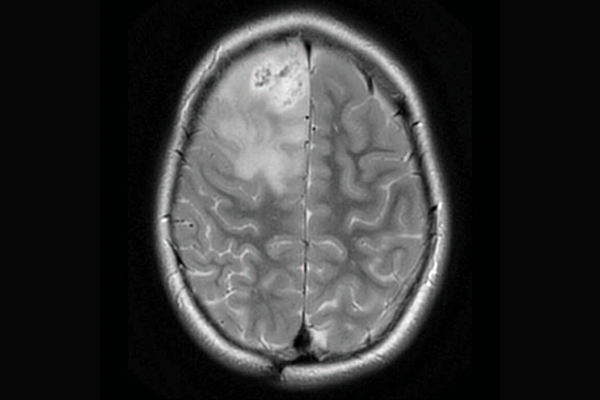

A scan of a brain with priMMRD subtype 3

priMMRD-1: The ultra hypermutant

These tumours are the most common, with 62 per cent of tumours having both MMRD mutations and polymerase proofreading deficiency (PPD), making them extremely sensitive to immunotherapy. A first-in-kind clinical trial called U-R-Immune Glioma, led by Drs. Eric Bouffet and Das at SickKids, is already pursuing an immunotherapy-first approach for these patients, sparing initial radiation therapy.